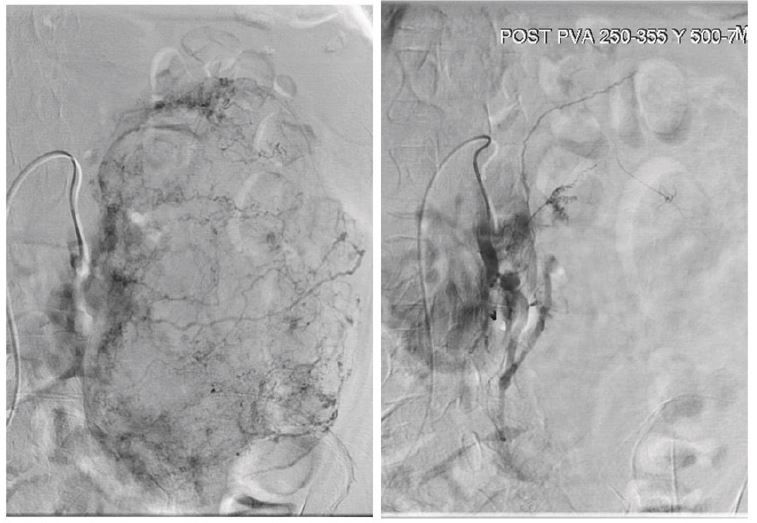

In patient B, the risk of surgical resection was found to be higher due to patient’s age and comorbidities. Selective embolization of tumor branches was successfully performed in order to minimize the risk of bleeding (Figure 5). No adverse effects were observed. After four months, the lesion had decreased in size, so we performed an open partial nephrectomy due to the patient’s favorable general condition.

Figure 5: Before and after selective renal embolization.